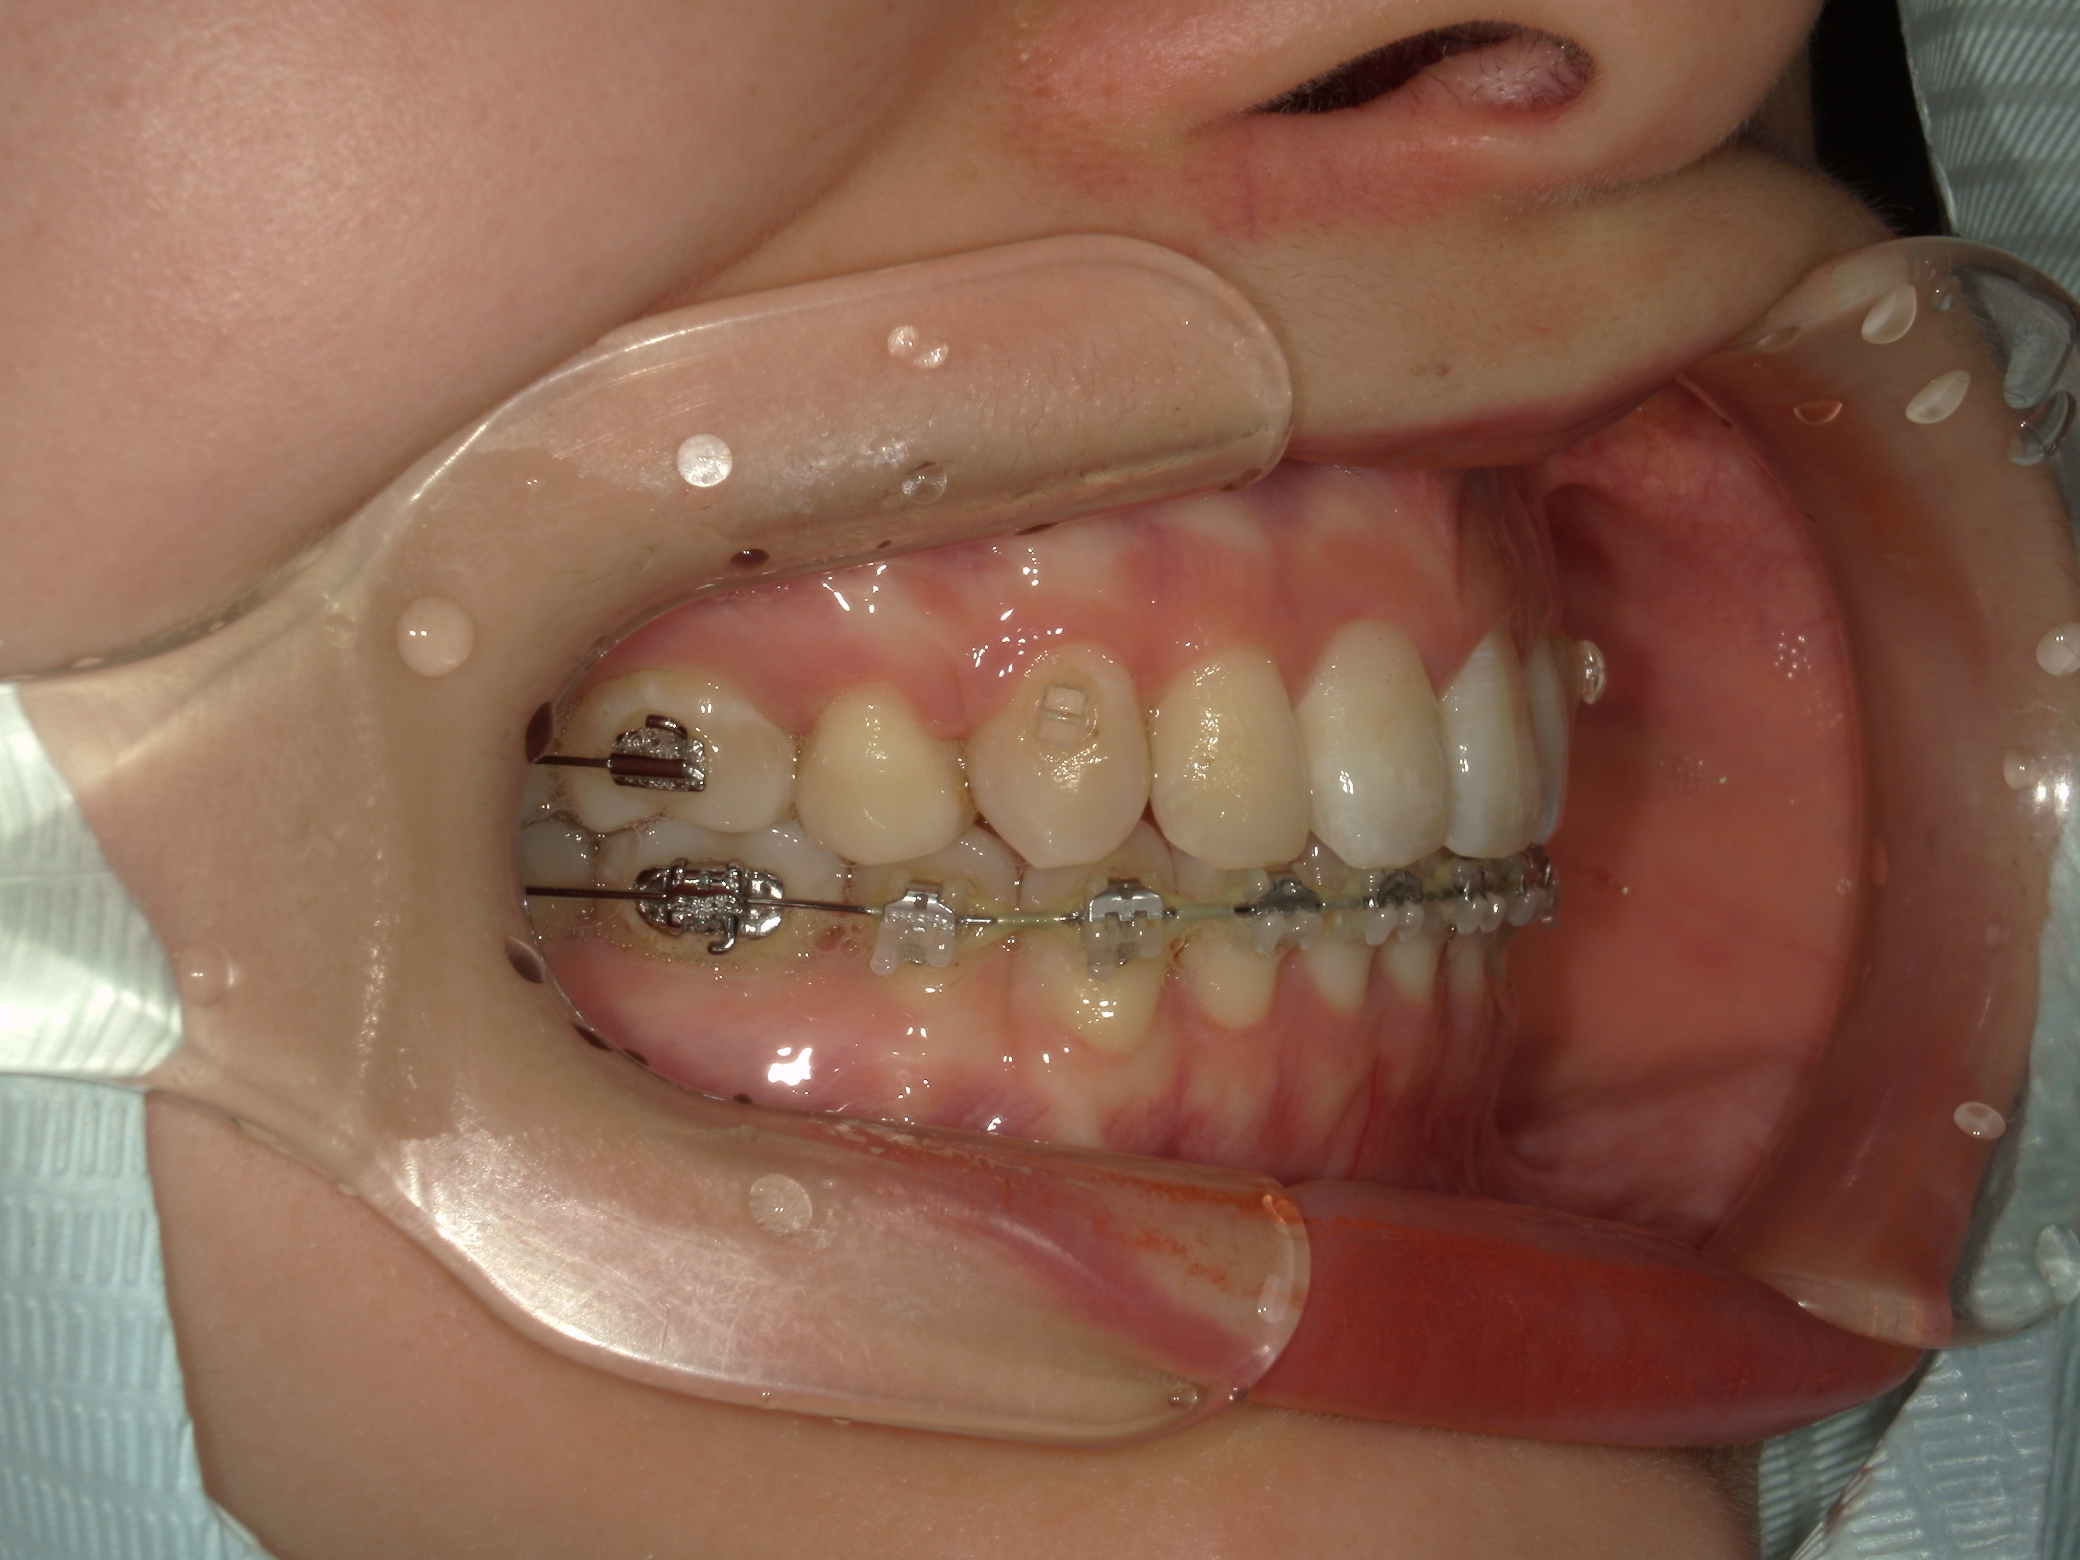

口元の突出を主訴に来院。

上下小臼歯抜歯により突出感を改善する計画を立てた。確立した咬合を崩さないように治療を進める事を目標とした。

患者はハーフリンガル矯正を希望した。

治療後、口元の突出感の改善、咬合関係は維持することができた。